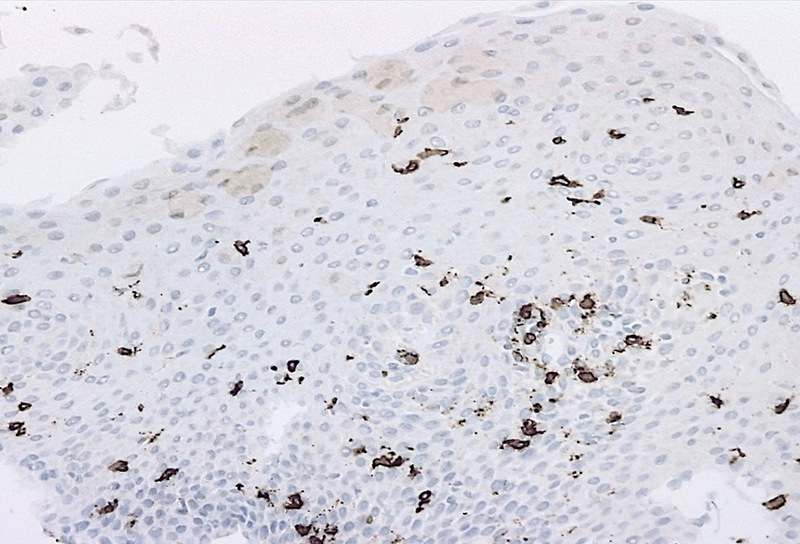

Microscopic examination revealed oesophageal squamous mucosa with an increased number of intraepithelial lymphocytes predominantly clustered around papillae, rare to absent granulocytes, intercellular oedema known as spongiosis and basal cell hyperplasia (Panels A and B). Most of the lymphocytes in the infiltrate were T cells CD3+ (Panel C). CD20 stain shows rare B cells (Panel D). CD4+ T cells outnumber CD8+ T cells (Panels E and F).

There is no standard number of intraepithelial lymphocytes required for diagnosis and studies have included various cut-off values, ranging from 20 to 50 lymphocytes/HPF.  A recently published consensus recommendation by an international expert panel suggests 40 lymphocytes per HPF as cut-off value, following Rubio’s initial criteria for diagnosis. Lymphocytic oesophagitis varies in the prevalence of CD4+ or CD8+ T cells. The predominance of CD4+ intraepithelial lymphocytes appears to be associated with dysphagia, primary oesophageal motility abnormalities and prominent spongiosis.